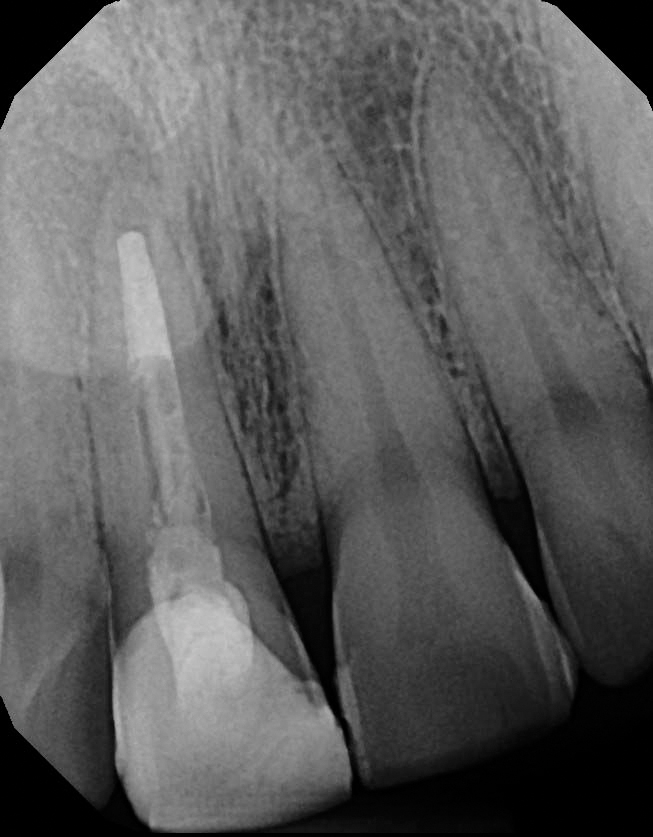

Straumann blt xray. Prophylaxis paste and cup 4. Bone level tapered implants blt refine. Implant blt the straumann bone level tapered implant comes in the materials roxolid with the slactive and sla surface or titanium with an sla surface a unified color code simplifies identification of instruments and im. X ray holder and film 2.

O 29 mm 1 o 33 mm 2 o 41 mm 2 o 48 mm. Straumannbone level tapered blt soft bone hard bone mandible in densifying mode make sure your osteotomy is 10 mm deeper than the actual implant final length. The straumann bone level tapered blt implant offers all the clinically proven features of the straumann bone level implant line plus the advantages of a tapered implant body. Implant blt straumann dental implant system.

In extreme hard bone utilize dac densify after cut protocol. Tissue level implants bone level implants. The shape surface and material combination are designed to deliver primary stability in all bone classes making the straumann bone level implant ideal for. Disposable saliva ejector and control pads 5.